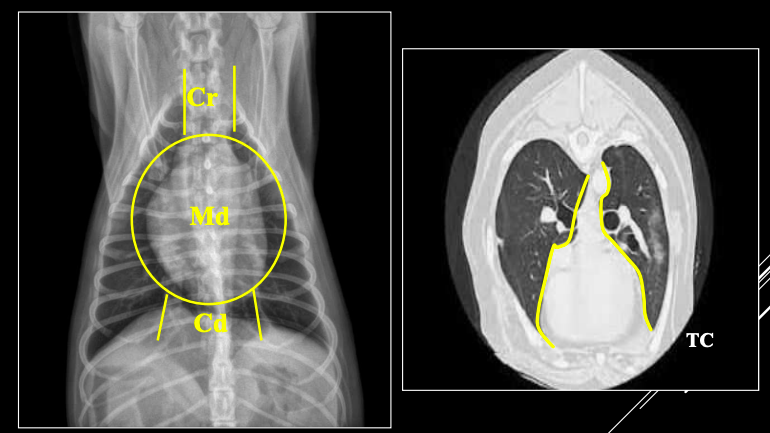

El mediastino es el espacio medio de la caja torácica, situado entre las pleuras mediastínicas. Importante

PARTES DEL MEDIASTINO

- Craneal (Cr): Nervios, nodulos linfaticos, vasos (Arteria subclavia izquierda, tronco braquicefalico, vena cava craneal, vena acigos...)

- Medio (Md)

- Caudal (Cd)

Órganos mediastínicos visibles:

- Esófago (a veces), timo (jóvenes), tráquea, corazón, aorta, VCC.

Órganos no visibles:

- Vasos (A. subclavia izda., tronco braquiocefálico, V. cava craneal, V. ácigos).

- Nervios.

- Nódulos linfáticos.